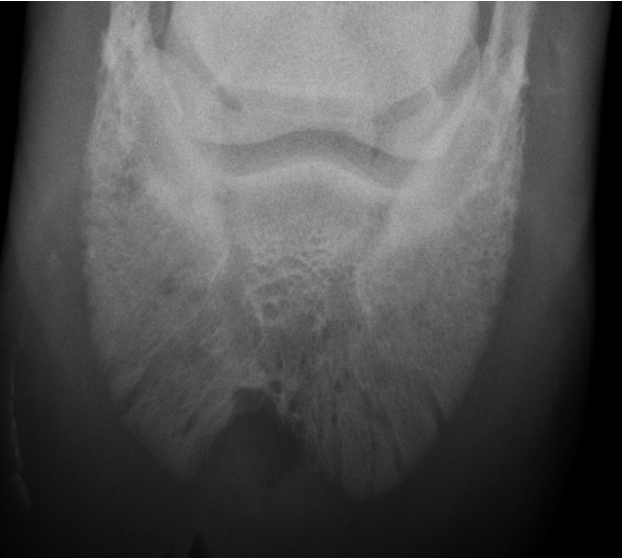

hypertrophic osteopathy signalment

middle to older dog

secondary to thoracic or abdominal dz/mass

spares small bones of carpus and tarsus

starts from MC/MT bones and goes up the leg symmetrically and bilateral

NO lysis but LOTs of periosteal rxn

AGG lesion

Hypertrophic Osteopathy